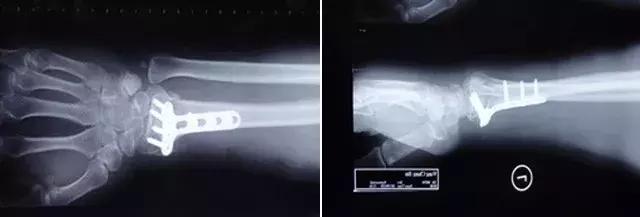

张大爷的骨折就属于不稳定的桡骨远端粉碎性骨折,早期虽然复位很好,但是随着患区组织肿胀的减轻,石膏就会出现松动,那么因为骨折端不稳定,复位可能就会出现不同程度的丢失,如果在不可接受范围,而这个时候可能已经错过了手法复位的理想时期,就基本需要手术复位了。